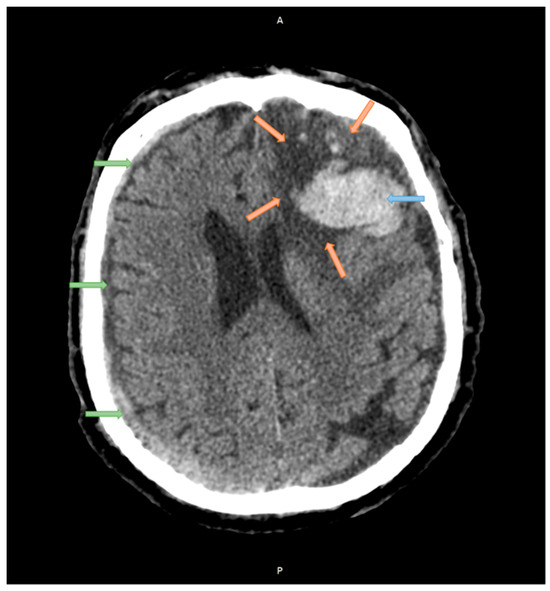

2.1. Case Studies